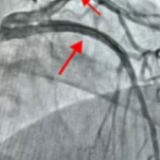

苏女士因“反复胸痛三天”入院,表现为心前区压榨性胀痛及绞痛,病情危急。经冠状动脉造影检查发现,其心脏最重要的血管之一——左前降支近段存在弥漫性狭窄伴严重钙化,最重处狭窄达95%。另一支重要血管左回旋支中段也存在重度狭窄,最重处达95%。这种如同被“钢筋铁骨”包裹的血管,传统介入器械难以充分扩张,手术难度极大、风险极高。

手术在数字减影血管造影(DSA)的精确引导及血管内超声(IVUS)的精准评估下进行。团队成员操作娴熟、配合默契,成功应用“旋磨+冲击波”组合拳,显著改善了血管的顺应性,最终顺利置入支架,血流恢复理想,患者转危为安。